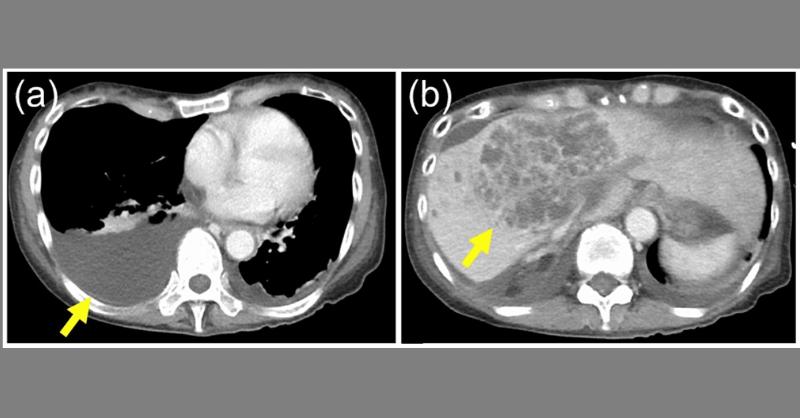

Diagnosis of Liver Abscess and Bacterial Cholangitis in a 67-Year-Old Woman

A 67-year-old woman with Primary Sclerosing Cholangitis (PSC) was presented due to a fever and was diagnosed with a liver abscess and bacterial cholangitis. Initial treatment with intravenous meropenem did not show significant improvement. Her condition deteriorated, leading to low blood pressure requiring noradrenaline, pleural effusion, and the n